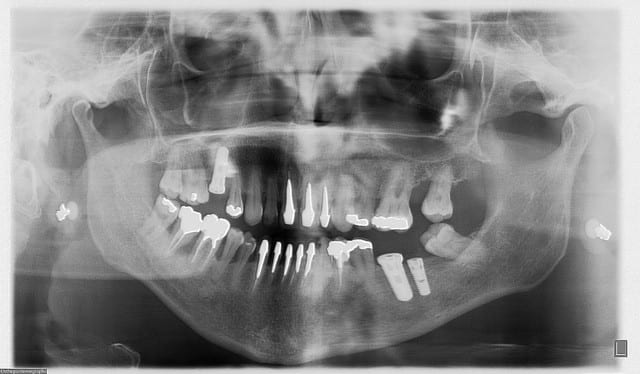

voilà un ptit cas de...disons 23 bis...car double agénésies des latérales...pas trop mal compensée naturellement secteur 1...mais persistance de la 63...à bout de souffle...

cette petite patiente ne veux pas d'ODF...mais ne veux pas rester sans dent...d'où cette intervention...avec la pose d'1 implant, avec expansion à l'aide de mon kit MIS... et mise en vitrine immédiate...